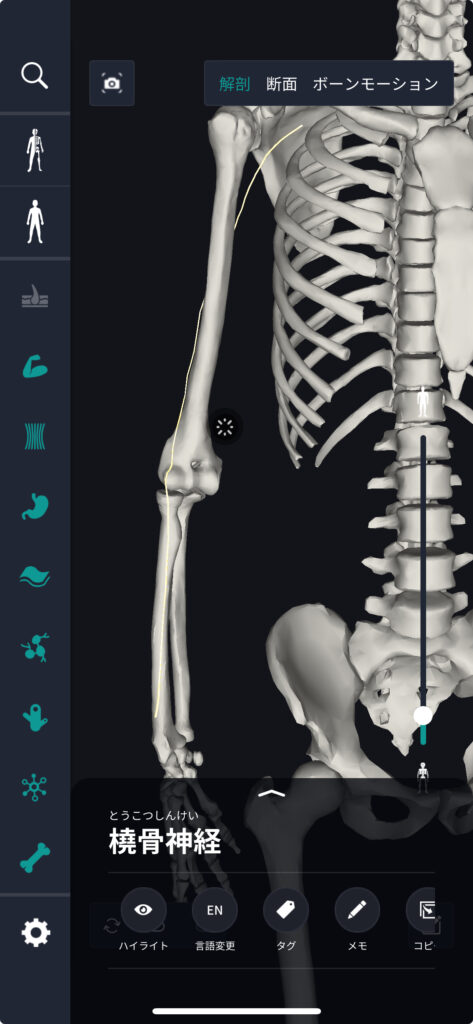

橈骨神経の場所・位置

橈骨肘を超えて前腕の後面を通り、指先に至る長い経路を持っています。前腕を通って指先に至る長い経路を持っています。人体解剖図を用いると、この神経の正確な位置と経路を詳しく学ぶことができます。

橈骨神経の覚え方

橈骨神経の位置を覚える一つの方法は、「親が子供を手首に導くように」というイメージです。親指から腕の内側を通り、前腕に沿って上腕に達する経路をイメージすると覚えやすいでしょう。